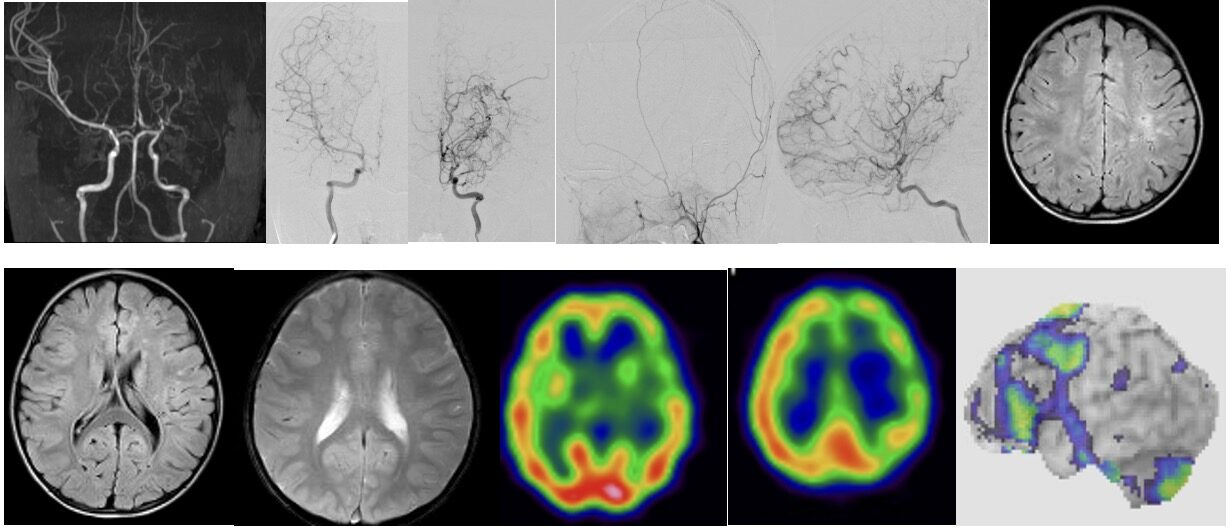

2025年6月 4歳女児 もやもや病バイパス術を行いました。術後トラブルなく元気に退院されました。